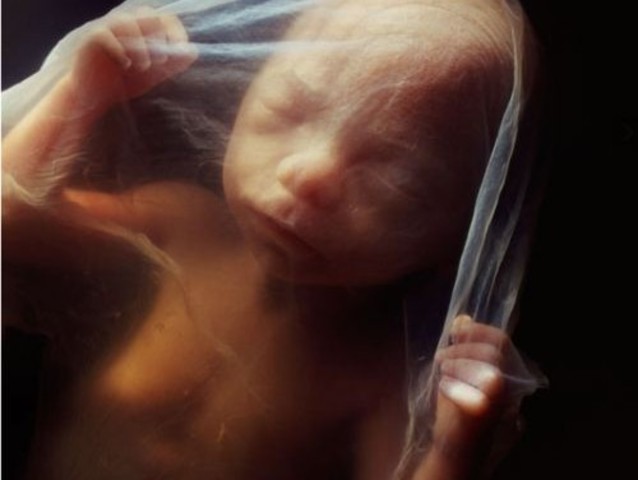

• Third Month

Third Month

Buds for future teeth start to appear.

Fingers and toes start to form. Soft nails start to form.

Bones and muscles start to grow.

The intestines begin to form.

The backbone is soft and can flex.

The skin is thin and transparent.

The hands are more developed than the feet.

The arms are longer than the legs.